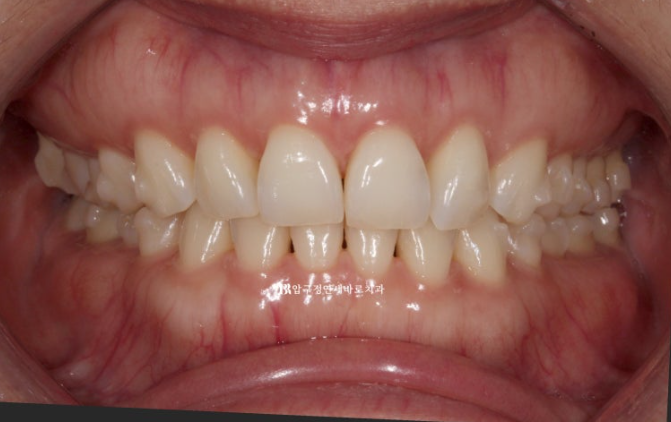

중심선 불일치 그리고 오른쪽의 맨 뒤 큰 어금니가 바깥으로 나가 있는 가위교합이 정면에서도 잘 보입니다.

23.07